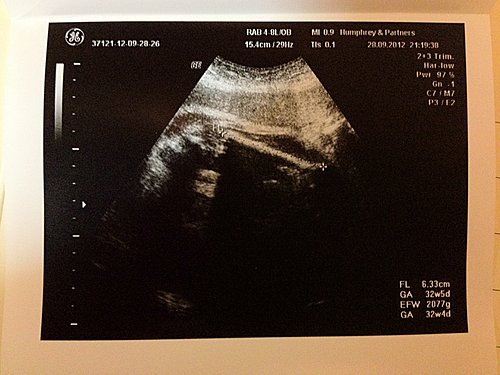

(阿 B 的頭圍)

(阿 B 的肚圍)

(阿 B 的大脾骨長度)

(阿 B 的腳板仔)

(阿 B 的心跳)

之後靳醫生仲幫我照埋阿 b 個 4d 樣,今次睇到呀,仲有正面睇添 (不枉我之前幾晚,同阿 b 傾計,叫佢唔好再用隻手遮住塊),不過一睇到阿 b 個樣時,我同老公,仲有靳醫生都一齊話,阿 b 塊面仔咁多肉嘅,好肥嘟嘟 wor,好彩靳醫生話阿 b 只係塊面前多 d 肉,個身型一 d 都唔係巨 b,而家係 100 個bb 入面,大約排 70 度,係中碼偏 size 的 bb 來~